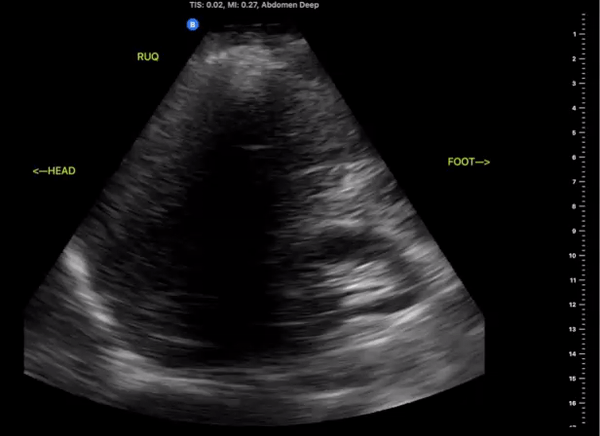

Right Upper Quadrant

(RUQ)

Probe/Preset:

Curvilinear, Phased Array/ FAST, Abdominal

Body Plane:

Coronal

Probe Indicator:

Towards Head

Depth:

At least 15cm

Location:

Mid axillary to anterior axillary line at the level of the xiphoid scanning posteriorly

Identify:

-

Right kidney

Liver

Diaphragm

Spinal Stripe

Notes:

The scan of the RUQ should be dynamic, starting at the interface between the lungs, diaphragm, and liver. Slide the probe towards the feet capturing views Morrison’s Pouch, inferior pole of the kidney and right Pericolic Gutter